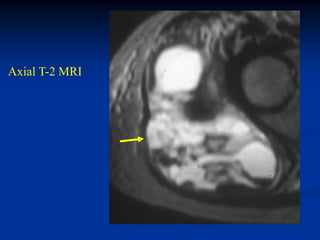

Case #1211.2               Synovial hemagioma knee

15 year male with knee pain for 6 months

Coronal T-1   Coronal T-2

Axial T-2

Surgical exposure at time of excisional biopsy

Case #1211.2 Synovial hemagioma knee 15 year male with knee pain for 6 months

• 363.

• 364.

• 365.

Surgical exposure attime of excisional biopsy